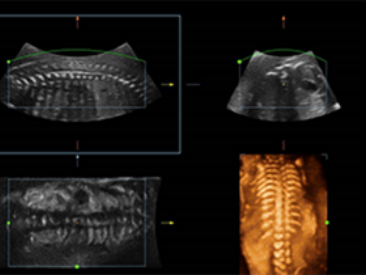

Obrazy kliniczne